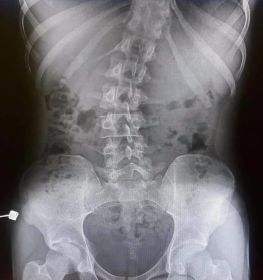

Skolyoz hastalığı omurgaların dizilimindeki düzensizlik ve yamukluktur. Çoğunlukla çocuklukta görülen hastalık yetişkinlerde de az da olsa görülebilir. Sağa sola omurgalardaki çıkıntıların zamanla omurilik eğriliği bir hale getirdiği hastalıkta erken tanı çok önemlidir. İster yetişkin isterse çocuk olsun erken teşhis sonucunda fizik tedavi yöntemi işe yarar. Hastalık özellikle kişilerin günlük yaşantılarını etkileyen olumsuzluklar yaşatan ve yaşam kalitesini düşüren bir rahatsızlıktır. Geç kalınmadan tedaviye başlanmalıdır.